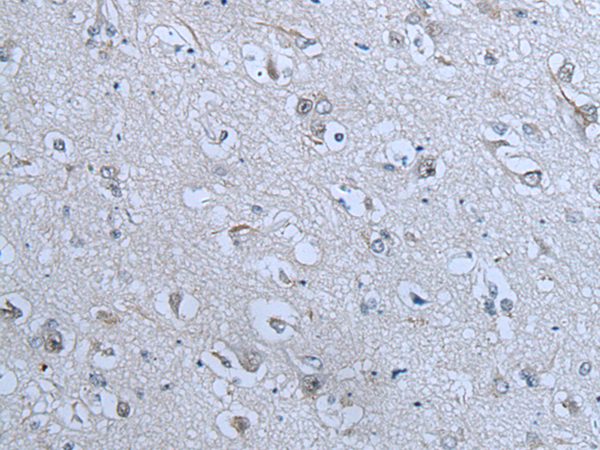

分类: 科研抗体货号: P12861别名:应用: IHC反应种属: Human, Mouse, Rat